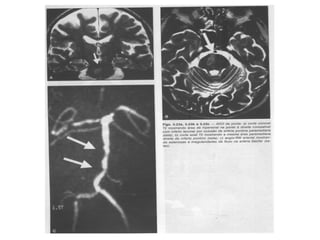

• HSA - HEMORRAGIA SUBARACNÓIDEA

Classificação quanto aomodo de instalação dos sintomas ÍCTUS = diminuição das funções do cérebro após uma alteração da circulação do sangue no mesmo • Icto completo (IC) – AVEH: – Hemorragia subaracnóidea (HM) • Comum na artéria comunicante posterior – causa tb paralisia completa do III n. craniano (oculomotor); • Pode causar tambem paralisia do pares IV (troclear) e VI (abducente).

• HSA -HEMORRAGIA SUBARACNÓIDEA